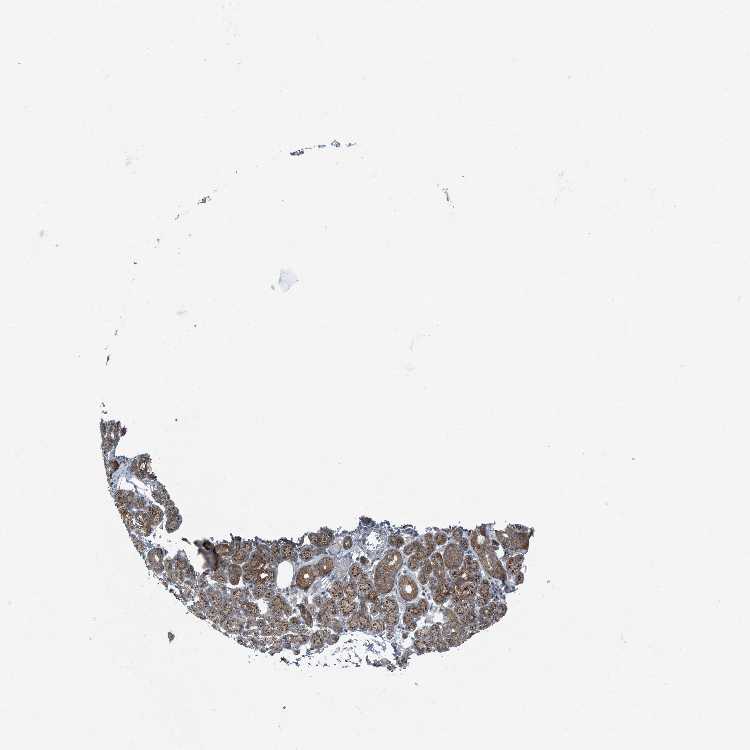

SALIVARY GLAND - Antibody stainingi

Antibody staining in the annotated cell types in the current human tissue is reported as not detected, low, medium, or high, based on conventional immunohistochemistry profiling in selected tissues. This score is based on the combination of the staining intensity and fraction of stained cells.

Each image is clickable and will lead to virtual microscopy that enables deeper exploration of all samples and also displays staining intensity scores, fraction scores and subcellular localization as well as patient and tissue information for each sample.

Antibody HPA035849Antibody HPA035850

Glandular cells MediumMedium